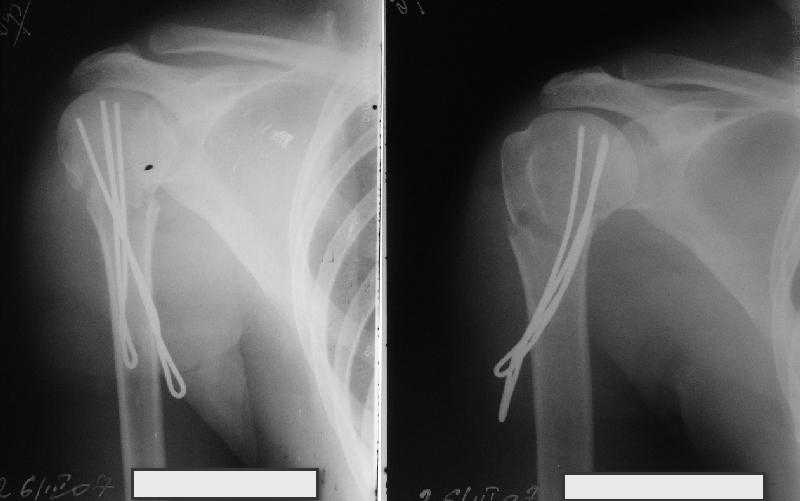

Очень даже неплохо получилось. Молодцы! Лучше чем на 3D "репозиции".

В приложении. Схема простая - по спице в каждый отломок, полукольцо проксимально, кольцо дистально, два телескопа. Как уже писал, ключевым моментом было введение спицы в плоскости диформации проксимального

оттдела плеча.